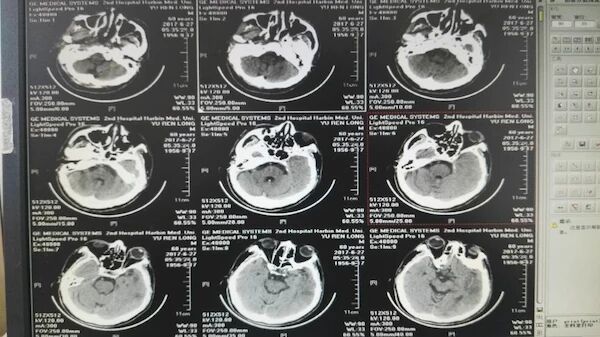

手术前的CT和多模MR